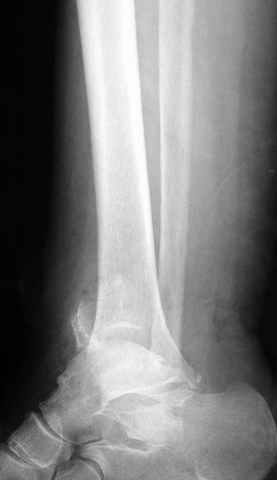

Pilon fracture:

-Появляется ориентир и остов, на чем можно строить восстановление, почему сперва малоберцовую, впервые обьяснили и описали (Pylon type and Ankle fractures) в середине 50х Rienau и Gay.

Восстановливая длину и ротацию малоберцовой кости, затем относительно легче произвести реставрацию остальных элементов перелома дистального эпиметафиза болшеберцовой кости.

где исследования на трупах показали, что малоберцовая кость участвует в стабильности голеностопного сустава, поддерживая наклон тарана (talar tilt) за счет связок. После ознакомления работой Ramsey в ортопедию ввели термин "при переломах голеностопного сустава смещенная

таранная кость следует за малоберцовой костью" т.е. связка не рвется, а тянет таран за собой, поэтому восстановление малоберцовой кости в

первую очередь, затем остальных элементов - стал классическим при лечении данной патолгии. Латеральная колонна (столб), дистальный

конец малоберцевой кости, к нему прикрепляется латеральный суставной фрагмент дистального эпиметафиза большеберцовой кости (как на снимке)

и таранная кость, которые при репозиции малоберцовой кости репонируются автоматически.

При косых переломах малоберцовой кости применение пластин отличается от обычных, показание antiglade technique-методика против скольжения, потому что укорочение длины малоберцовой кости чреваты ранними артрозами.

Из работ Ramsey and Hamilton, Yablon et., укорочения на 1мм

малоберцовой кости, уменьшает на 42% контактную поверхность между

малоберцевой и таранной кости, которое в свою очередь приводит к

увеличению давления на остальные части суставной поверхности, что

является предпосылкой раннего артроза.